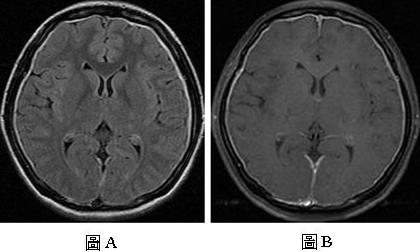

【110-1 醫學(四) 第75題】26歲女性患者,主訴姿態性頭痛已經一個星期,接受磁振造影檢查,圖A是FLAIR影像,圖B是注射顯影劑後的T1加權影像,下列何者是最可能的診斷?